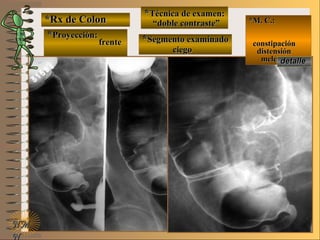

a ver lasa ver las

imágenesimágenes

En estas radiografías en proyección de frente seEn estas radiografías en proyección de frente se

deben distinguir los distintos segmentos gástricos,deben distinguir los distintos segmentos gástricos,

la distribución de los pliegues y la presencia dela distribución de los pliegues y la presencia de

áreas gástricas que nos permiten aseverar que laáreas gástricas que nos permiten aseverar que la

mucosa del estómago esta indemnemucosa del estómago esta indemne

**Opción avanzada para volver a ver las imágenes con reparosOpción avanzada para volver a ver las imágenes con reparos

NMNM

D. F. M.D. F. M.

UNTUNT

E ME M

*Rx de Estómago*Rx de Estómago

**Proyección: frenteProyección: frente

**Técnica de examen:Técnica de examen:

A-“relleno total”A-“relleno total”

B- “mucosografía”B- “mucosografía”

C- “doble contraste”C- “doble contraste”

**Segmento examinado:Segmento examinado: